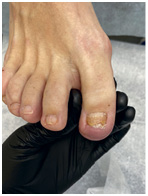

Результат работы за 5 месяцев: подолог использовал крючковые коррекционные системы, а хирург сделал пластику внутреннего бокового валика (из-за хронических воспалений боковой валик стал гипертрофированным и давил на ноготь, от чего клиент испытывал постоянный дискомфорт)